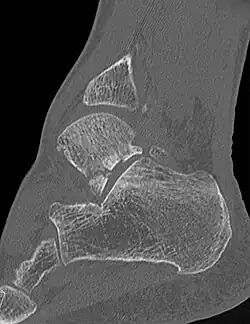

Die Verletzung stellt sich mit Schmerzen und Schwellung in der Fußwurzel und außen am Fuß dar. Diese Befunde können leicht mit einer Verstauchung, Zerrung oder einem Bänderriss am Außenknöchel verwechselt werden. Dieses insbesondere, wenn nicht bekannt ist, dass es sich um einen Snowboarder handelt. Auch ist der Knochenbruch auf Übersichtsröntgenbildern manchmal schwer zu erkennen. Eine Computertomographie kann die Bruchlinien überlagerungsfrei darstellen und ist für die Planung der richtigen Therapie hilfreich.[6][14][7][12]

Die Möglichkeiten der Behandlung hängen von dem Typ der Fraktur ab. Wenn das äußere Bruchstück groß genug ist (über 1 cm, Typ II nach McCrory-Bladin), kann selbst bei nur geringfügiger Dislokation eine operative Refixation mit Minifragment-Schrauben erfolgen. Eine solche Refixation scheint gegenüber der konservativen Behandlung einen Vorteil für den Patienten zu ergeben.[15] Aber auch die Entfernung von Kleinfragmenten unter 1 cm (Typ I) oder von Trümmerfragmenten einer Typ-III-Fraktur aus dem Gelenkbereich kann zu einem besseren Ergebnis führen, wenn eine Refixation nicht möglich ist.[16] Die konservative Therapie sollte in einer Gipsruhigstellung in einer leichten Spitzfußstellung erfolgen, sie ist aber komplikationsanfällig und im Wesentlichen bei den Patienten empfohlen, bei denen eine Kontraindikation gegen eine Operation vorliegt, da sie häufig zu einer schmerzhaften Pseudarthrose führt, die dann sekundär eine Exzision oder sogar eine subtalare Arthrodese notwendig werden lässt.[17]